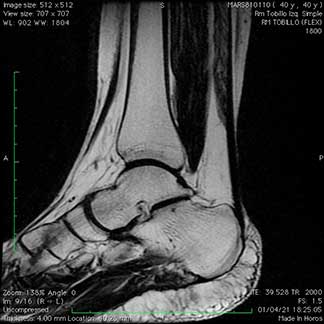

Ligamentosas o ligamentarias con distensiones y rupturas totales o parciales.

Vasculares, nerviosas, articulares y óseas que se traducen en fracturas conocidas como edema óseo.

Pueden afectar las articulación del cuello, hombros, tórax, pelvis, caderas, muslos, rodillas, piernas, tobillos o el pie, es decir, cualquier estructura del cuerpo está expuesta o tiene el riesgo de sufrir una lesión.